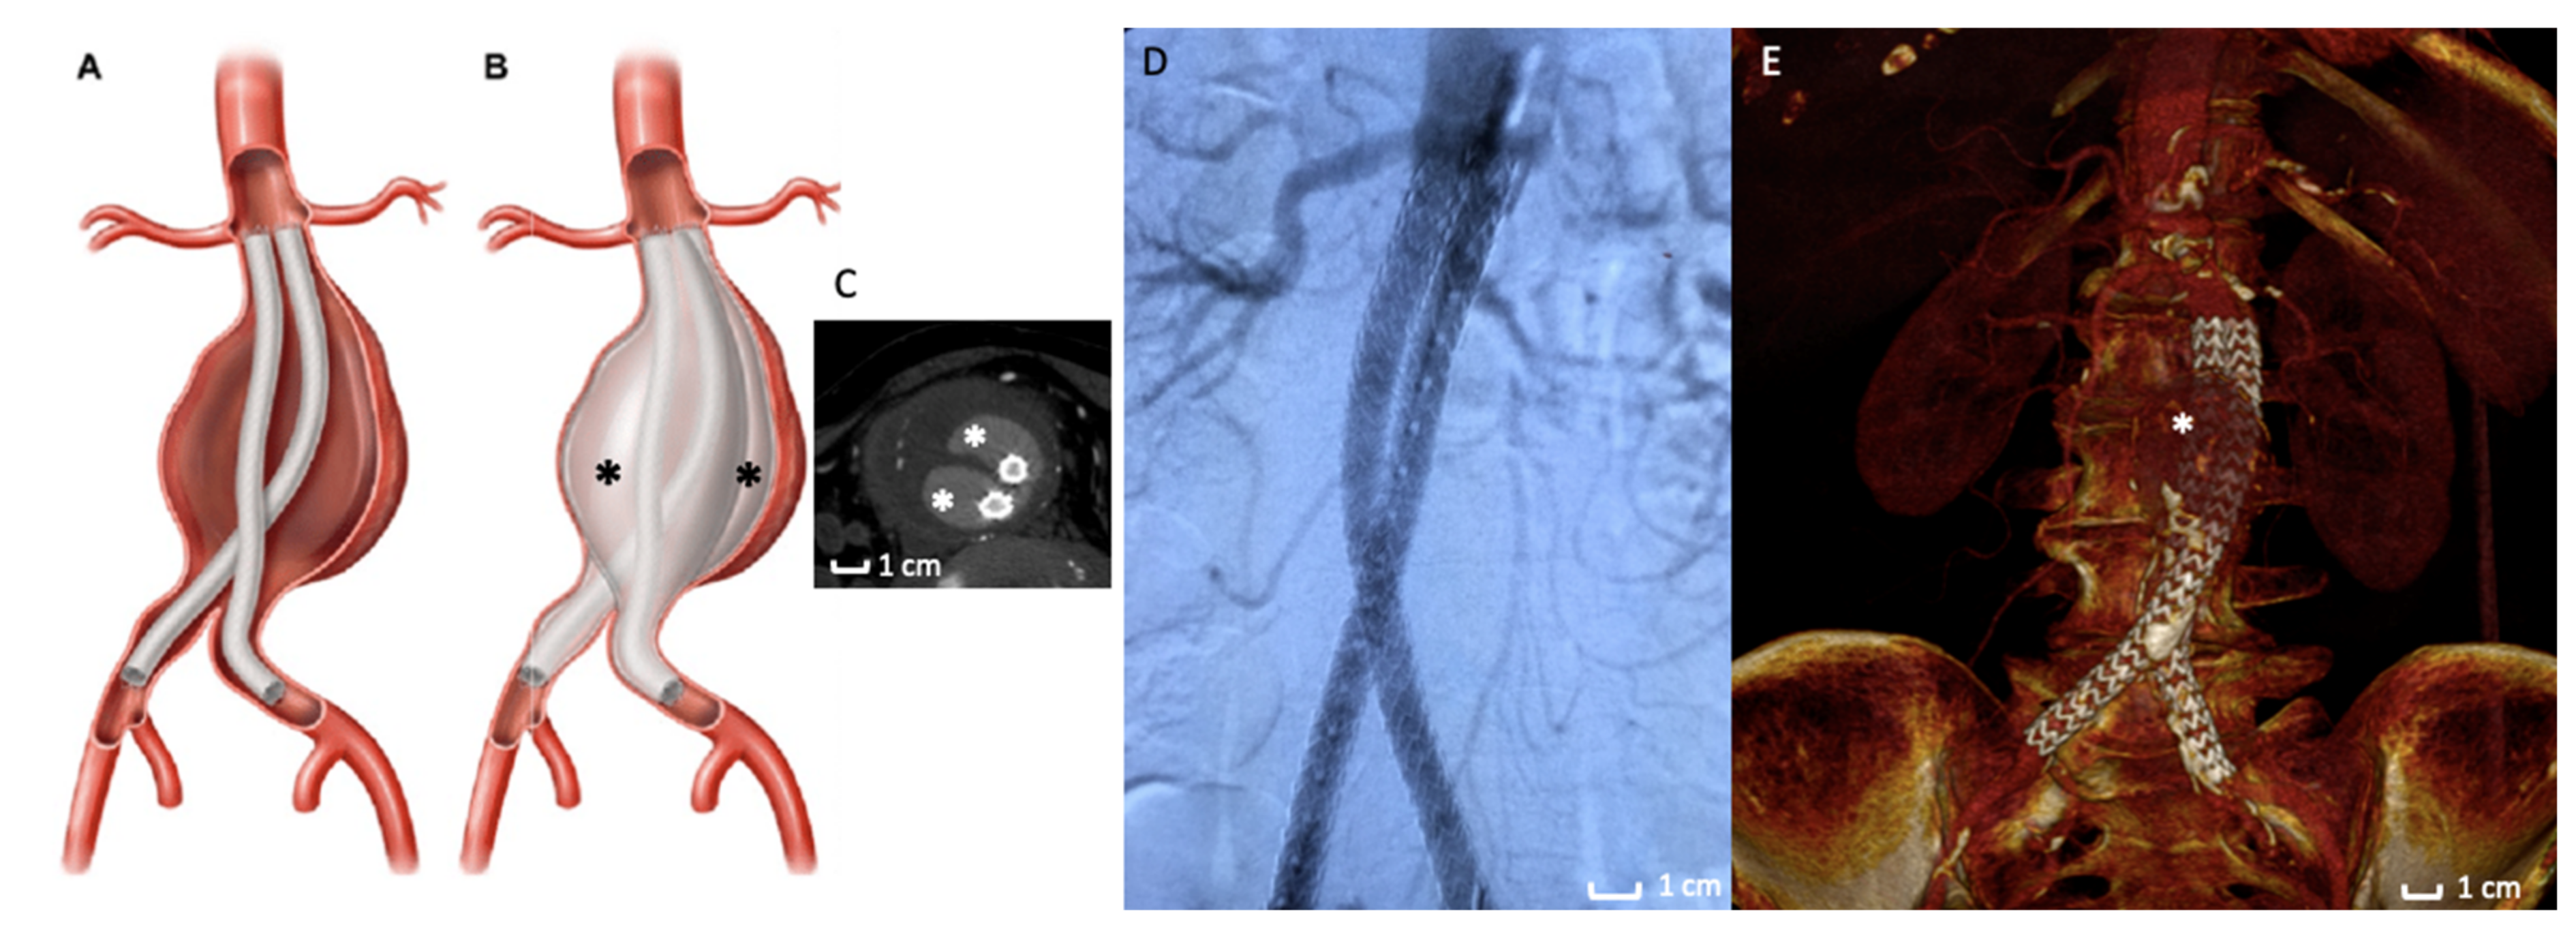

The use of polymer as an alternative to traditional SESGs is a fascinating field in endovascular techniques. Two different stent graft designs combined with a polymer technology have been proposed for clinical application in the treatment of AAAs: (1) the polymer-filled endobags, so-called Endovascular Aneurysm Sealing (EVAS) with Nellix stent graft (Figure 2); and (2) the O-ring EVAR polymer-based proximal neck sealing device, so-called Ovation stent graft (Figure 3).

Figure 2.

Nellix stent graft. (A,B) Picture of Nellix endograft during the endobags’ polymer filling maneuvers. The asterisk (*) indicates the endobags that adapt to the morphology of the entire aneurysm sac. (C) Axial Computed Tomography Angiography detail of a Nellix endograft implanted. The stent grafts (arrows) are located in the middle of endobags, which are filled with polymer (*). (D) Intraoperative image of the Nellix stent graft deployed with angiographic contrast medium that highlights the good patency of the endograft and the exclusion of AAA. (E) 3D volume rendering of Computed Tomography Angiography at 3-months follow-up post-implantation that reveals a good aneurysm exclusion. The asterisk (*) indicate the polymer-filled endobags.

The Nellix System (Endologix Inc., Irvine, CA, USA) for endovascular aneurysm sealing (EVAS) was introduced as a novel approach to the treatment of AAA [58] in 2013. The EVAS procedure is conceptually distinct from EVAR: the Nellix device is designed to seal and obliterate the aneurysm lumen and not to exclude it (Figure 2B,C).

The device consists of two balloon-expandable stents supporting the aorta flow channel. The system is inserted into the aorta in a similar way to EVAR. By using guidewires, the system is advanced into the aorta through the femoral arteries. The catheter sheaths are then pulled back, deploying the device, which expands from the non-aneurysmal aorta proximally to the iliac arteries distally. The non-porous PTFE-based endobags are then filled with the biocompatible polyethylene glycol polymer (Figure 2B,C), which adjusts the endobag to fit the aneurysm sac lumen. The bio-stable cross-linked polymer inflating the endograft envelope in opposition to the aortic wall mimics the process of injection molding. Thus, high conformability is achieved, as the device is molded in-situ to the specific patient anatomy to accomplish a customized seal. Once this configuration is completed, the polymer cross-links to form a ‘personalized’ prosthesis [59].